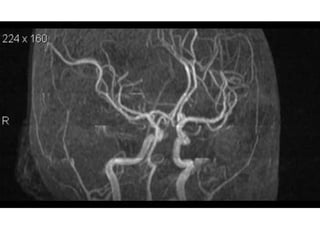

NORMAL MRA

Arteries of the brain (cranial view) - MRA

Arteries of the brain (lateral view) - MRA